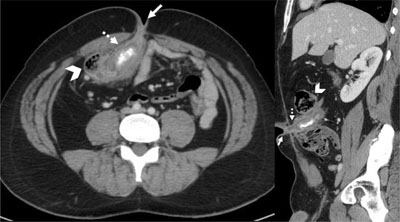

Computed tomography (CT) of the abdomen revealed a dilated and thickened intestinal structure, extending from the caecum toward the umbilicus and containing a calcified deposit (Figure 2). These findings were consistent with appendicitis of the appendicostomy with appendicolith.

Coronal reformatted and axial contrast medium-enhanced CT-scan images showing dilated and thickened intestinal structure (dotted arrow) between the caecum (arrowhead) and the umbilicus (arrow), containing a calcified deposit.